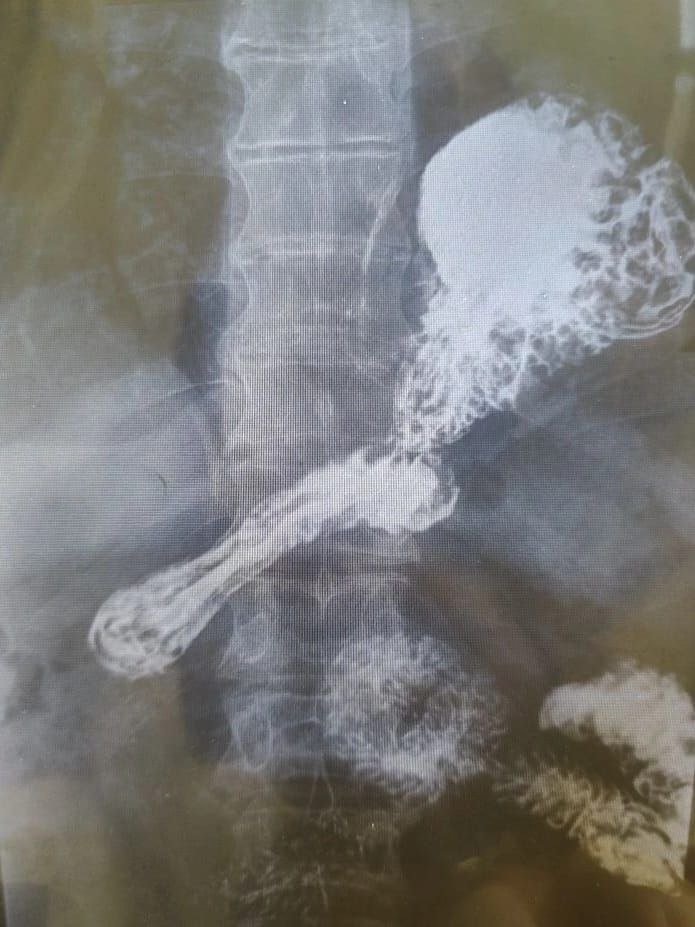

Снимок грыжи. Фото: Пресс-служба Краевой клинической больницы № 2

"Четвертая степень заболевания характеризуется смещением всех поддиафрагмальных структур в плевральное пространство. Иными словами, желудок пациента полностью находился в его грудной полости. Как следствие — постоянная изжога, отрыжка, затрудненные глотание и дыхание, загрудинные боли. Желудок сдавливал перикард, сердце и легкое, существовал высокий риск ущемления грыжи. Состояние стало для человека мучительным и представляло серьезную угрозу для его жизни", — приводит пресс-служба слова заместителя главного врача по хирургии Андрея Мерена.